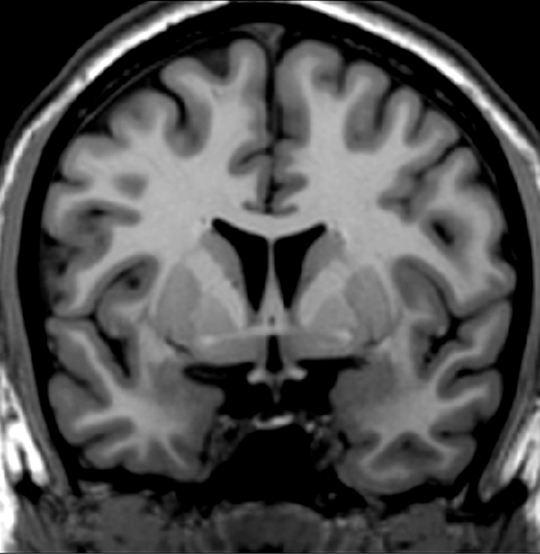

Bilateral destruction of this structure (and adjacent cortex) in primates results in dramatic changes in emotional behavior, ie. affective blunting-docile, no expression of anger or fear etc., referred as Kluver-Bucy syndrome. Locate this nuclear group.